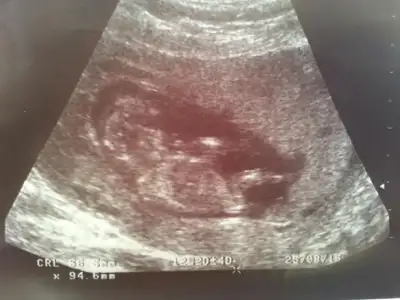

merhaba benim bebişiminde resmi bu 11-3 haftalıkken yorum yapabilirmisiniz

• CAM01704[1].webp

CAM01704[1].webp

29,8 KB · Görüntüleme: 117